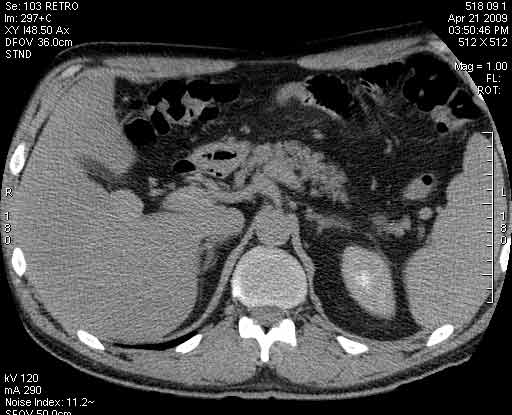

Пациент с клиникой острого холецистита на фоне ЖКБ.

В печени выявлен гипоэхогенный очаг неокруглой формы, аваскулярный при цветовой доплерографии.

Сонограммы, КТ- артериальная, портальная и отсроченная паренхиматозная фазы

Простая и одновременно "сложная" задачка. По УЗИ; явный стеатоз печёночной паренхимы (теперь ключевые слова); на ФОНЕ СТЕАТОЗА определяется гипоэхогенное образование. Варианты? Очаговое образование; и менее вероятно участок гипостеатоза (но не похоже, есть чёткие границе, + не та локализация).

Сделали КТ (весьма похвальная тактика); по КТ: в артериальную фазу: периферическое усиление в виде сливающихся островков контраста, с центрипетальной направленностью. Венозная и отсроченная фаза-хорошее накопление контраста; образование практически изоденсно по отношению к паренхиме печени. Классика гемангиомы. Вуаля-диагноз на "тарелочке".

Вывод: надо иметь ввиду, что эхогенность это относительное понятие, эхогенность гемангиомы может изменятся при изменении положения обследуемого пациента (см. прикреплённую статью); не надо забывать что эхогенность образование это понятие относительное, т.е. относительно окружающей паренхимы печени! При стеатозе, гемангиома может выглядеть гипоэхогенно по отношению к гиперэхогенной паренхиме окружающей печени. И главное, есть сомнение-заказываем таргетное мультифазовое КТ.